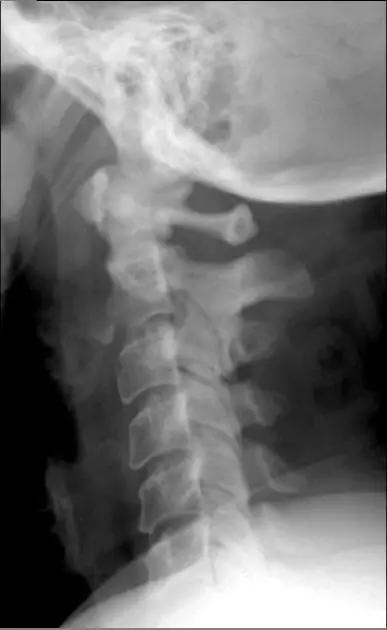

2. Teardrop 骨折

特指颈椎椎体前下方带有骨折块者,包括屈曲型和伸展型。伸展型损伤指椎体前下缘或下一椎体前上角形成三角形骨块,提示椎体前方稳定结果破坏,治疗不宜伸展位。屈曲型指压缩致使椎体前方三角骨块被挤出如泪滴状,提示前后方稳定结构均遭破坏,常伴脊髓损伤。常需手术治疗。

伸展型 Teardrop 骨折(来源:Radiopaedia)